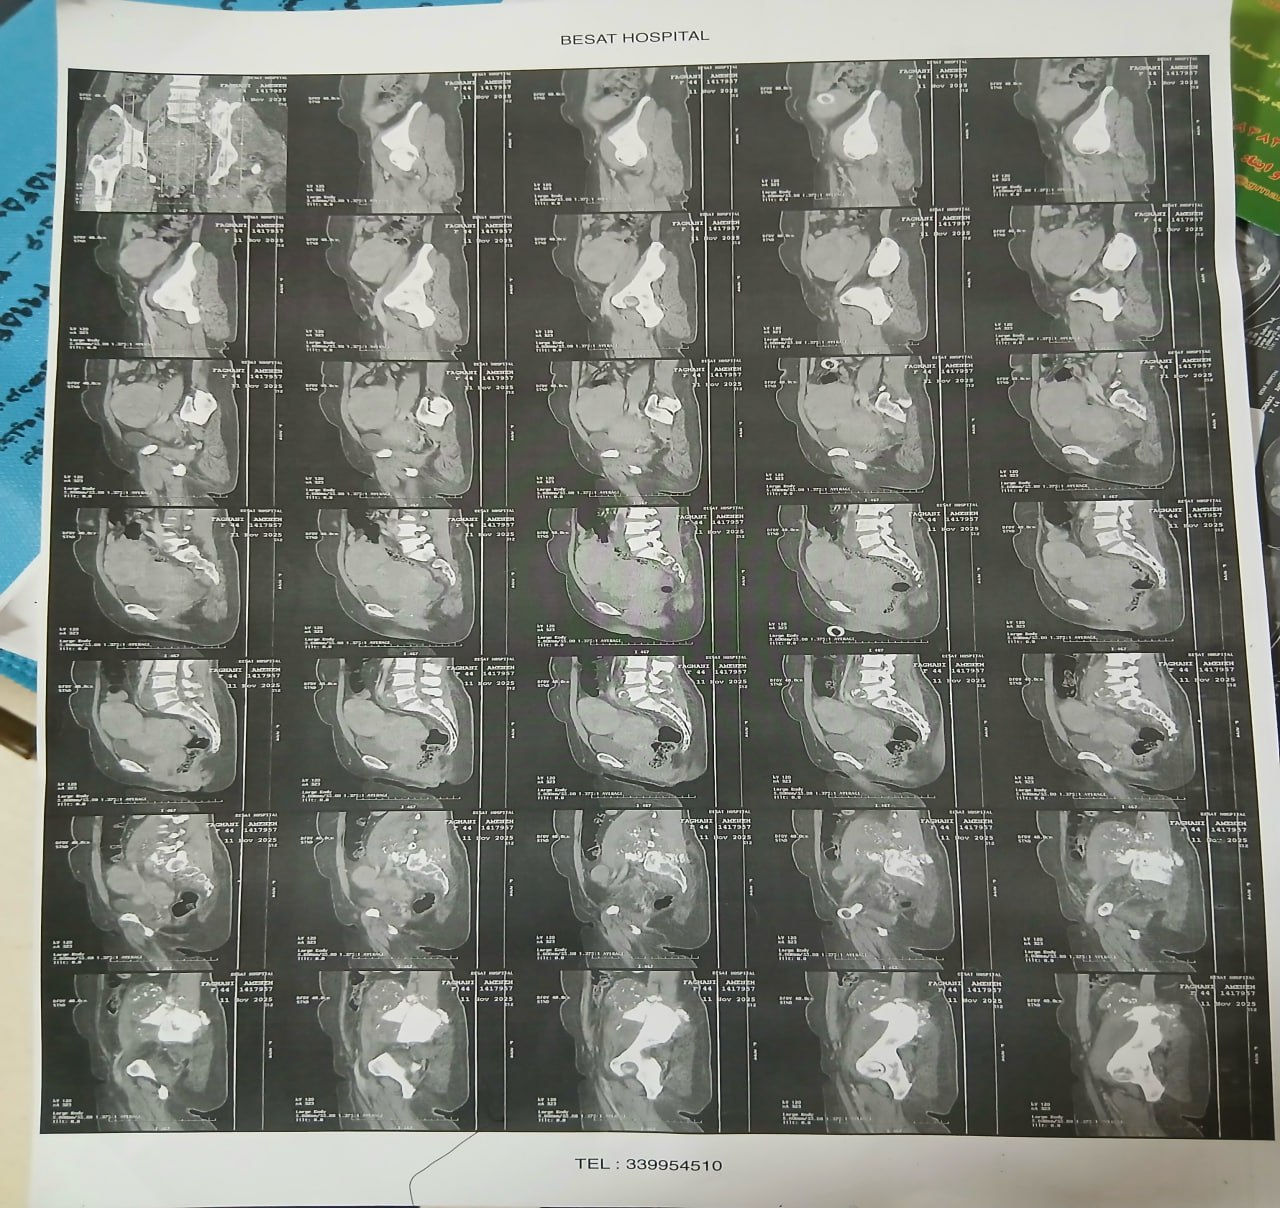

در بررسیهای تصویربرداری (MRI)،در تاریخ 24.7 ، تودهای با تشخیص کندروسارکوما همراه با DVT گزارش شده است. بیمار سابقه درد لگن داشته که شدت آن در حال حاضر نسبت به گذشته کاهش یافته است. به گفته بیمار، حجم توده در ابتدا در حدود اندازه یک تخممرغ بوده که در حال حاضر کاهش یافته است. همچنین تورم اندام تحتانی در حال حاضر نسبت به قبل کمتر شده است.

مراجعه کرده است. پس از بررسی های انجام شده در MRI انجام شده توده با درگیری مفصل ساکروایلیاک چپ و DVT؛ ابتدا تحت درمان DVT قرار گرفته است و سپس جهت پیگیری تومور رویت شده تحت بیوپسی قرار گرفته است و با تشخیص کندروسارکوما به این مرکز مراجعه کرده است و تحت کموتراپی و رادیوتراپی قرار گرفته و سایز تومور کاهش یافته است.

(تصویر مربوط به این مراجعه نیست) Other: